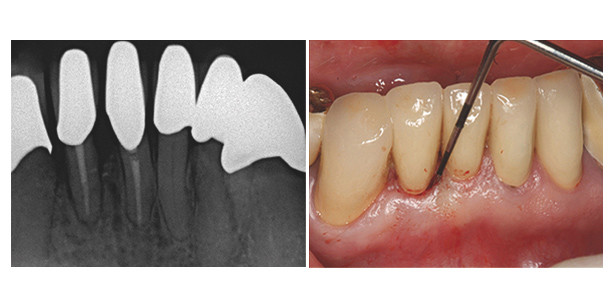

Für eine erfolgreiche Behandlung von Paro-Endo-Läsionen ist ein spezielles Therapiekonzept erforderlich. Am Beispiel von zwei Fällen wurden...

Im Nachfolgenden wird die Behandlung einer entzündlichen Gingivasituation um Metallkeramikkronen im oberen Frontzahnbereich beschrieben.

Vereinzelte Rezessionen und Stillman Clefts teils in Kombination mit keilförmigen Defekten – all diese Probleme können beim PA-Patienten...